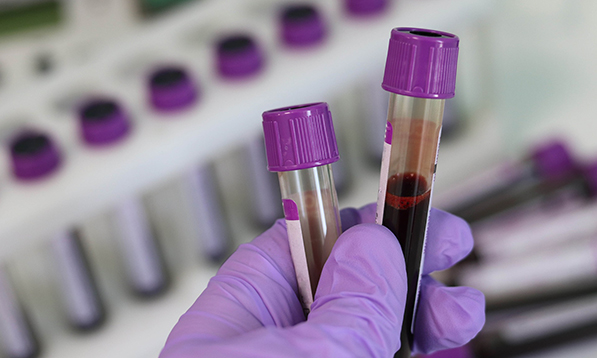

Iako se dugo pretpostavljalo da je ovako nešto veoma moguće, ipak, dosadašnjim metodama, mikroplastika nije mogla biti izmerena u ljudskoj krvi i samim tim to nije moglo biti dokazano. Međutim, istraživački tim ekotoksikologa sa Vrije Univerziteta u Amsterdamu, je prvi koji je to dokazao. Naime, oni su razvili jednu metodu pomoć u koje su po prvi put mogli da tačno izmere koncentracije mikroplastike u ljudskoj krvi. Kao što su i sumnjali, plastika sa kojom se srećemo najčešće bila je prisutna i u ljudskom krvotoku. Tim je testirao 22 osobe na 5 najčešće korišćenih tipova plastike u svakodnevnom životu i otkrio da čak 17 uzoraka sadrži male količine mikroplastike, što je 77% ispitivanih uzoraka. Najčešći tip detektovane plastike je bio PET, od koga su sačinjene uglavnom plastične flaše, kese i ambalaže raznih namirnica iz marketa. Količina plastike koja je pronađena je vrlo mala i odgovara jednoj kašičici plastike na 1000 litara krvi, ali je dovoljna da izazove veliku zabrinutost zbog mogućeg štetnog uticaja na zdravlje. Krv povezuje sve delove tela pa se samim tim mikroplastika može naći u bilo kom organu našeg tela.

Jedno od ograničenja ovog rada jeste veoma mali uzorak; odnosno, u istraživanju su učestvovala samo 22 ispitanika i nema informacija o tome koliku su izloženost plastici ovi ispitanici imali u svom životu. Takođe, u radu nije utvrđena veličina pronađene mikroplastike niti broj ovih čestica, što bi bilo veoma važno istražiti u budućnosti. Međutim, i samo otkriće da je mikroplastika prisutna u krvotoku je dovoljno da se shvati važnost i urgentnost ovakvih ispitivanja, kojih mora biti više u budućnosti. Ova studija doprinosi dokazima da mikroplastika ne prožima samo životnu sredinu već prožima i naša tela, a dugoročne posledice toga još uvek nisu poznate medicini.